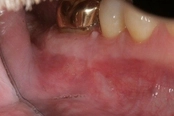

Lower molar failed root canal, microsurgery saved the tooth:

Before

Immediately after

3-month follow-up with complete healingThis patient presented with a failed root canal. The root canal became infected. An apicoectomy (apical microsurgery) was performed using the laser. Patient had minimal swelling, minimal discomfort, and fast healing. The tooth was saved and an implant avoided. This tooth tends to have a lower success rate with root canal therapy; thankfully apical microsurgery was available to save the tooth.

At the 3 month follow-up, the gums look like nothing was done thanks to the skill and use of the laser for the procedure.